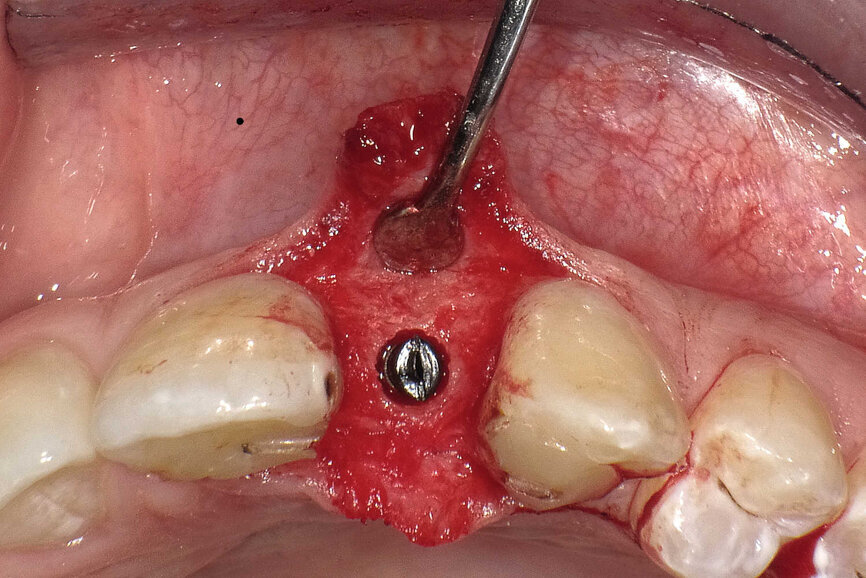

Fig. 6 : Les implants (Bicon Dental Implants) sont insérés jusqu’à 2–3 mm sous le niveau de la crête. Une vis de cicatrisation en PTFE noir d’une épaisseur de 2 mm protège l’implant pendant la période de cicatrisation.

L’implant a été mis en place au moyen d’un instrument spécial pour l’insertion d’implant, qui permet au praticien de pousser l’implant fermement, en appliquant une pression précise dans l’ostéotomie (Fig. 5). La dernière étape a consisté à introduire complètement l’implant au moyen du maillet, et de l’instrument d’insertion fixé à la poignée de serrage droite. L’implant étroit était dès lors bien positionné entre les deux racines (Fig. 6). L’implant de 8 mm de long et de Ø 3 mm a été inséré par l’application d’une pression dans l’ostéotomie, et l’utilisation du maillet et de l’instrument d’insertion à 3 mm sous le niveau de l’os crestal (Fig. 7). La seconde phase du traitement a été réalisée après six mois de cicatrisation et a consisté à désenfouir l’implant. Un pilier ayant un corps de Ø 2 mm et une base hémisphérique de Ø 4 mm a été choisi pour connecter les couronnes provisoires à l’implant. Il est important de veiller à la bonne cicatrisation du tissu mou autour du contour coronaire adéquat, et celle-ci peut être obtenue par une modification du profil d’émergence de la couronne provisoire jusqu’à la formation des papilles. Après la cicatrisation complète du tissu mou, la dernière empreinte a été prise et la couronne définitive a été scellée sur le pilier en titane (Figs. 8 et 9).